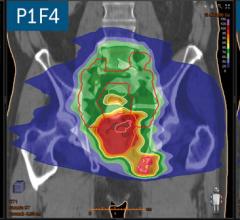

Treatment Planning

Having a treatment plan is an important part of radiation therapy. This channel page includes news and new technology innovations for treatment plans.

Plan optimization and dose calculation for complex VMAT plans are computationally challenging tasks. Depending on the ...